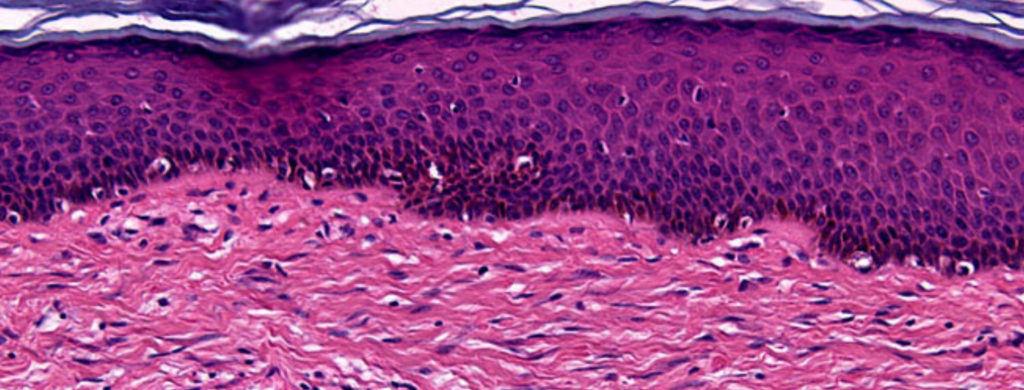

In healthy fascia, the collagen fibers are woven together in a cohesive way like fabric. It has structural integrity that allows for some movement and stretching in certain directions and also limits movements in others. When healthy, it acts like an ACE bandage already built into your joints, muscles, tendons, and ligaments.

In scar tissue, the collagen fibers are thrown into place like a pile of pick up sticks. The body has to stop the bleeding from an injury quickly. It doesn’t have time to carefully arrange the collagen fibers for structure and healthy movement. If you have any noticeable skin scars you can attest to the difference. Healthy skin moves and stretches, while a scar feels hard and immobile.